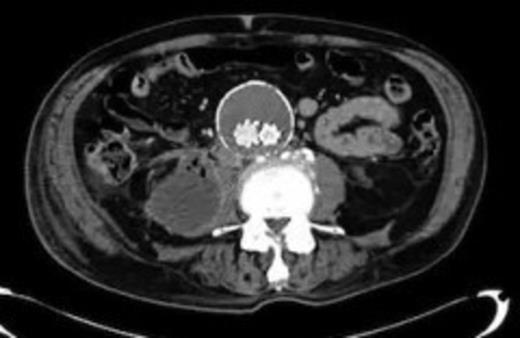

Four weeks following discharge the patient was re-admitted with feeling increasingly unwell, recurrent pyrexia, loss of appetite and mild shortness of breath on exertion. Physical examination was unremarkable except for a temperature of 38.3 centigrade. Blood tests on admission showed Hb 11.4 g/dl (11.5-16.0 g/dl), white cell count 13.1×109/L (4-9.2 x 109/L) and CRP 68mg/L (<3 mg/L). Contrast enhanced CT scan (Fig. 2,3) showed a 50 mm maximum retroperitoneal collection situated between the right kidney and the right iliac vessels. It contained a few loculi of gas. A diagnosis of postoperative right psoas abscess was made. The patient was started on intravenous broad spectrum antibiotics – Tazocin (Piperacillin+ Tazobactam) and Metronidazole. CT guided drainage was carried out using a 10 French gauge pigtail catheter locked pigtail (Meditech Flexima regular all-purpose drainage catheter sets with locking pigtail (Boston Scientific)) (Fig. 4). The isolation of E. coli from the collection with negative Hemocultures suggested a bowel source for the infection but no actual breach was demonstrable. The bowel surgeons ruled out colonic pathology.

CT guided drainage was carried out using a 10 French gauge pigtail catheter locked pigtail (Meditech Flexima regular all-purpose drainage catheter sets with locking pigtail (Boston Scientific))